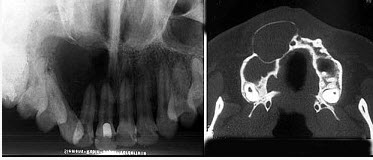

98、单项选择题

位于上颌侧切牙与尖牙之间的非牙源性囊肿(影像检查如图)是()。

A.球上颌囊肿

B.鼻腭囊肿

C.正中囊肿

D.鼻唇囊肿

E.角化囊肿